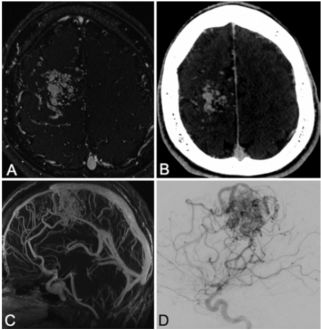

15.颅内积脓引流后即刻还纳骨瓣的疗效分析

Efficacy of immediate replacement of cranial bone graft following drainage of intracranial empyema.

DOI:10.3171/2018.3.PEDS17509.

颅内积脓若不及时诊断和正确处理,可能会导致患者死亡,并遗留严重的神经功能残疾。本文作者介绍了他们中心的经验,即开颅清除脓肿术后立即还纳骨瓣,并阐明了该方法在颅骨完整性、降低感染复发风险和减少二次手术可能等方面的有效性。

作者回顾分析了19年间(1997-2016年)诊治的脑脓肿患者资料,33例患者接受了脓肿急诊引流+去骨瓣减压术,随访时间超过6个月,其中23人即刻还纳骨瓣。对患者的以下临床资料进行了分析,包括人口统计学信息、感染的范围和部位、骨瓣的大小和固定方法、再次手术干预的可能性以及静脉使用抗生素的疗程。患者术时的平均年龄为8.7±5.7岁,感染大多数继发于鼻窦炎(52.8%),最常见的部位是额叶/颞叶(61.3%)。手术去除了31个骨瓣,平均表面积为22.8±26.9 cm2。初次手术还纳的几乎所有(96.8%)骨瓣长期都具有活力。18名患者(78.3%)需进行一次去骨瓣手术联合抗生素治疗,以解决感染问题;而剩下的21.7%患者需要1次以上的手术。在31个成功复位的骨瓣中,只有1例(3.2%)骨瓣部分重吸收。该患者最终去除了原来的骨瓣,接受了分离式颅骨修复术。21名患者(91.3%)接受了术后CT扫描,以评估颅骨的完整性,平均随访时间为43.9±54.0个月。本研究结果表明,颅内积脓去骨瓣引流术后即刻还纳骨瓣,其感染复发的风险低,是一种恢复颅骨完整性安全有效的方法。

![]()